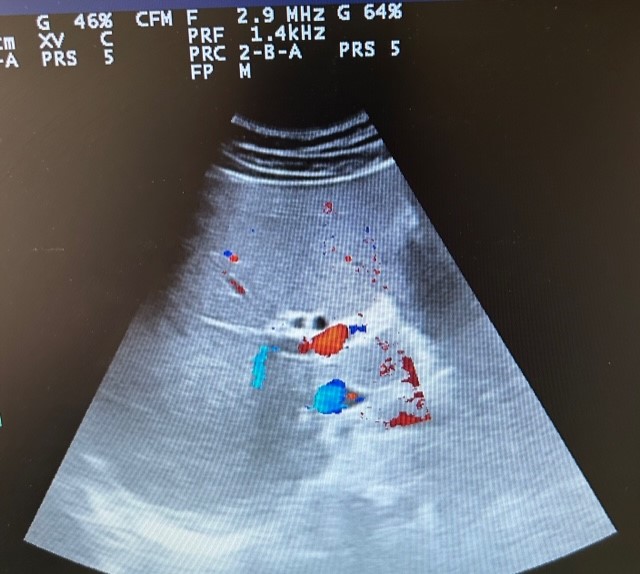

En la ecografía se observa ectasia de la vía biliar intrahepática conformando un patrón de doble carril.

No se visualizan colelitiasis.